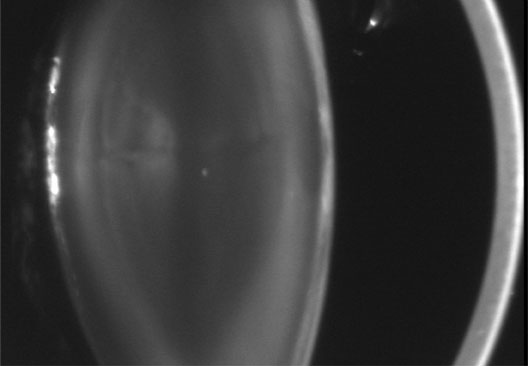

Anterior lenticonus (Figs. 8 and 9) is considered an integral part of AS. The anterior capsule thins and allows the lens to bulge into the anterior chamber, using the pupil as a mold.53 Electron microscopy of the renal glomeruli and anterior lens capsule can confirm capsular thinning and dehiscences.54,55 Anterior lenticonus is typically diagnosed in the second and third decades of life, when it causes clinically significant decreased vision,56 but it may be present in adolescence and result in spontaneous rupture of the anterior lens capsule.57 Posterior subcapsular cataract occurs quite frequently; however, many patients receive glucocorticosteroids for their renal condition, which may play an etiologic role in these cataracts. Additional ocular features described in XLAS include other corneal dystrophies, microcornea, corneal arcus, iris atrophy, posterior lenticonus, spontaneous lens rupture, spherophakia, a poor macular reflex, fluorescein angiogram hyperfluorescence, electrooculogram and ERG abnormalities, and retinal pigmentation abnormalities.58

Fig. 8. AS. The thinned lens capsule and anterior cortex protrude centrally into the anterior chamber and an additional small, central, posterior, subcapsular opacity in a 38-year-old male with AS (Scheimpflug image).